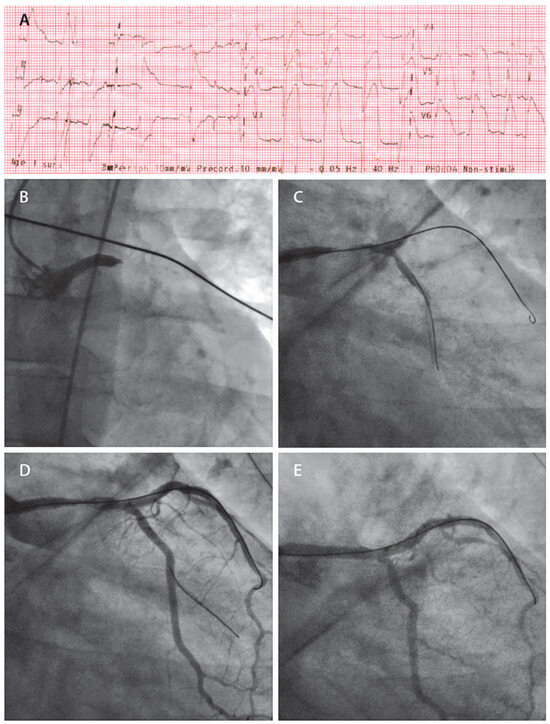

Transcoronary Alcohol Ablation—On Behalf of Three Cases with Hypertrophic Obstructive Cardiomyopathy

by Alexander Breitenstein, Jasmina Alibegovic, David Hürlimann, Patric Biaggi, Roberto Corti and Thomas F. Lüscher

Hypertrophic cardiomyopathy (HCM) is a common genetic disorder with an estimated prevalence of 1:500. About a quarter of the patients with HCM have left ventricular outflow tract obstruction referred to as hypertrophic obstructive cardiomyopathy (HOCM). Even with optimal medical treatment using negative inotropic drugs such as β-blockers and first generation calcium-antagonists, about 5–10% of patients with HOCM remain refractory to therapy. In such cases, reduction of the outflow gradient by either surgical myectomy or catheter-based alcohol septal ablation represent further treatment options. Even though myectomy historically is considered the gold standard, interventional alcohol ablation of the septum has become the treatment of choice in many centres. We present the history of three patients suffering from HOCM, who were successfully treated by catheter-based alcohol septal ablation. Full article

Figure 1